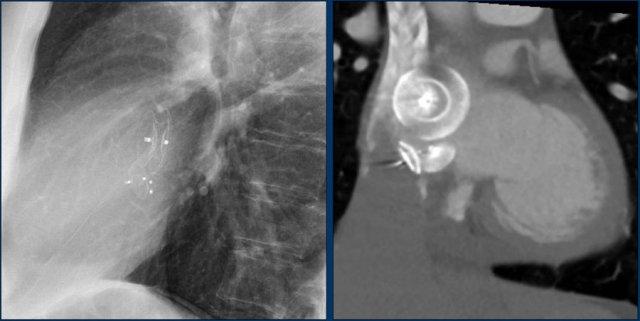

Bệnh nhân này đã được sửa chữa ba van:

- Van hai lá

- Van ba lá

- Van động mạch chủ

Có máy tạo nhịp tim với điện cực thượng tâm mạc.

Phương án này được lựa chọn vì người ta cho rằng điện cực đặt theo đường thông thường vào thất phải sẽ ảnh hưởng quá nhiều đến chức năng của van ba lá nhân tạo.

Mũi tên trắng chỉ vào van động mạch chủ.

Mũi tên vàng chỉ vào van hai lá.